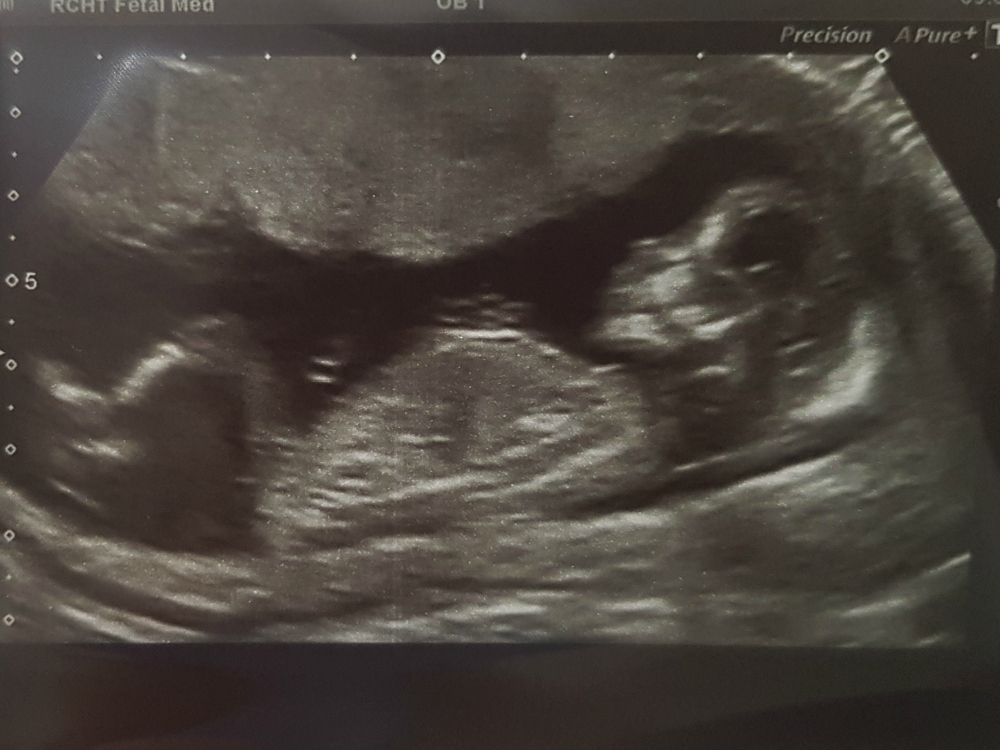

We just had our scan, and are so happy that baby looks healthy.

We had the Ramzi at 8 weeks - and it was saying boy (also predicted boy correctly last time)

I think boy for sure now, and am feeling no GD, just so happy baby 2 is healthy.

He has long legs like his Papa, and I can't wait to meet him.

So just for fun what are you thinking from skull, boy too ?!